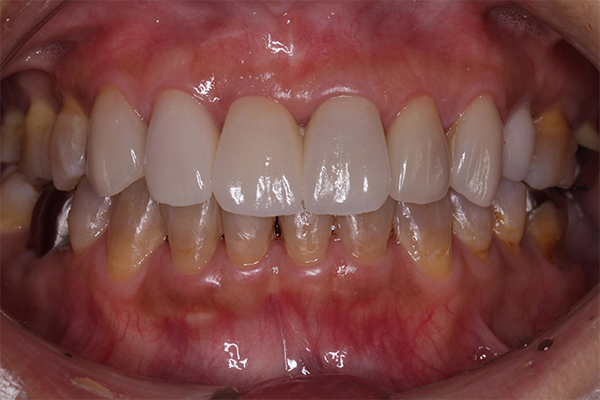

主訴は「全ての歯を綺麗に治したい」とのことで来院されました。診断の結果、複合的な問題が見つかり、歯周病治療、矯正治療等複数の治療を約3年ほど順番に進めていきました。最終的には歯の色味も回復させることができ、患者さんにも満足していただけました。

| 患者 | 45歳 女性 |

|---|---|

| 主訴 | 前歯が取れた。 |

| 診断 | このケースはかなりひどい叢生があり、矯正治療が必須であると説明。 |

| 治療内容 | 左上5は保存不可能のため、右上より5を左上に移植 矯正終了後補綴治療 |

| 治療期間 | 約3年半 |

| 費用 | 200万円 |